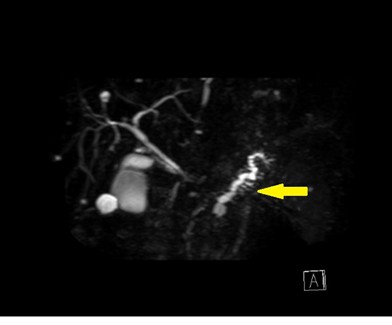

その中でもMRCP(磁気共鳴膵胆管造影)という撮影法は、胆管や膵管を強調して映し出す方法で、小さな病変や、膵管のわずかな拡張や不整を発見するのに非常に有効です。

@先ほどの症例のMRCP画像。膵管の拡張がありました。